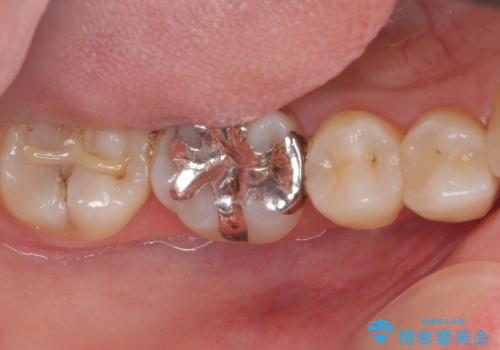

- 下の奥歯(右下7・左下7)にあって目立ってしまう銀歯を白くしたいとのことで来院された患者様です。

セラミックインレーにて修復治療を行うこととしました。

セラミックインレーを装着したことで、とても自然な仕上がりとなりました。

患者様も大きく口を開けても気にならなくなった、大変喜んでくださいました。